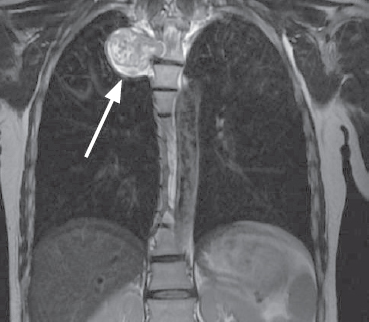

По данным магнитно-резонансной томографии грудного отдела позвоночника паравертебрально справа на уровне тел позвонков Th5 визуализируется образование гантелеобразной формы, размерами 9 × 39 × 35 мм, исходящее из правого корешка Th5; правое межпозвонковое отверстие расширено (рис. 1, 2).

Рис. 1. Магнитно-резонансная томограмма грудного отдела позвоночника, коронарная проекция, опухоль указана стрелкой

Fig. 1. MRI of the thoracic spine, coronal view, the tumor is indicated by an arrow